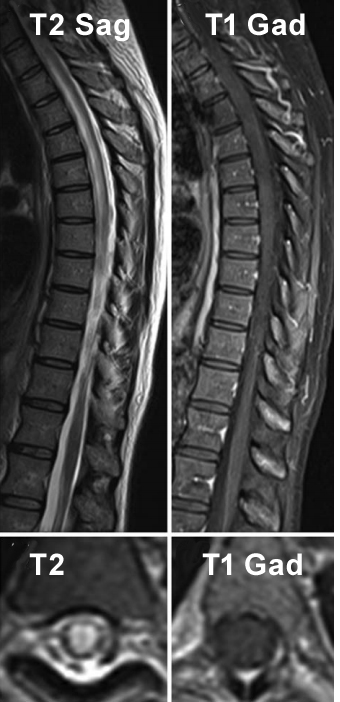

Q10: 41 year old patient presents with a rapid onset of paraplegia. He is found to be HIV positive. CSF shows elevated total protein (0,8 g/L), a mild pleocytosis (19 lymphocytes/µl), and a glucose value of 3.2. Oligoclonal bands were negative. T1 weighted s.